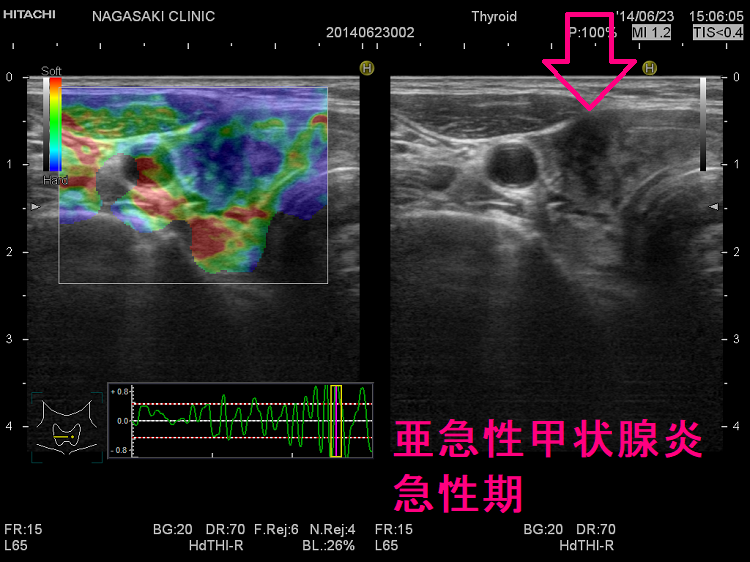

長崎甲状腺クリニック(大阪)オリジナルの亜急性甲状腺炎の治療は、中途再燃・再発を防ぐため、超音波(エコー)検査で炎症範囲を毎回調べ、改善度に応じてステロイド量を調整。炎症の強い部分は黒く、血流乏しく、エラストグラフィーで青くなる。副作用チェックはステロイド肝障害・膵炎・筋障害・低カリウム血症・糖尿病。甲状腺乳頭癌の合併、亜急性甲状腺炎ではなく、甲状腺乳頭癌の事も。亜急性甲状腺炎はバセドウ病,橋本病に合併、あるいは誘発する事も。頚部腫大、甲状腺中毒症が先行する場合、エコー検査で偶然見つかる事も。数年かかっても完全治癒しない亜急性甲状腺炎も稀に存在。

エラストグラフィーを用いて亜急性甲状腺炎が永続性甲状腺機能低下症に至るかを判定する試みがあります。石川県立中央病院の報告では、硬さの指標ストレインレ-ト(strain ratio)が大きいと、永続性甲状腺機能低下症になりやすいとされます(第57回 日本甲状腺学会P2-053 亜急性甲状腺炎経過後に、永続性甲状腺機能低下症に至る要因に関して)。

下は亜急性甲状腺炎の超音波(エコー)画像で、炎症の強い部分は黒く、エラストグラフィーでは青くなります。